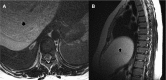

CSF pseudocyst: an unusual cause of back pain